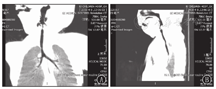

60例咽喉部特殊结构异常患儿中,鼻塞/张口呼吸7例(11.67%),憋气39例(65.00%),喉鸣44例(73.33%),呛奶和声嘶各25例(各占41.67%),吞咽困难18例(30.00%)。19例(31.67%)患儿并多种畸形及合并症,如先天性心脏病、VCTERL综合征、腭裂、马蹄内翻足、食管裂孔疝等。47例(78.33%)并肺炎。除依据临床表现,辅助检查是确诊的重要手段(图1、图2),60例患儿中依靠鼻咽喉镜确诊者52例(86.67%),依赖增强CT确诊者10例(16.67%)。73例喉软化患儿均依靠鼻咽喉镜确诊。

注:声门下区气管左侧壁局限性增厚伴强化,并向腔内突入。局部呼吸道变窄,病变范围1.1 cm×0.4 cm×0.5 cm。相邻左侧梨状隐窝受压外移并变窄;声门下呼吸道左右径窄 The left side wall of the trachea in the subglottic region was thickened with enhancement,protruding into the cavity.Extent of disease 1.1 cm×0.4 cm×0.5 cm.The adjacent pyriform recess is narrowed by compression.The glottis airway has a narrow left and right diameter

先天性喉裂是罕见的先天性上呼吸道畸形[7]。喉裂和气管/食管裂可单独发生,或作为某一综合征(如Opitz-Frias综合征、VATER/VACTERL综合征、Pallister-Hall综合征、CHARGE综合征)的一部分发生,或并其他相关畸形(累及胃肠道、泌尿生殖道、心脏和颅面等)。喉气管食管裂的治疗取决于其类型和相关症状的严重程度[8,9]。本研究中有喉裂患儿4例,预后均较差。增强CT可能有助于显示较大的血管瘤或超出喉范围的血管瘤。采用普萘洛尔的全身性治疗是声门下血管瘤的一线疗法[10,11,12]。本研究中新生儿期诊断2例声门下血管瘤,辅助检查具有典型表现,1例患儿放弃治疗,1例患儿口服普萘洛尔,6个月随访状况良好,瘤体变小。